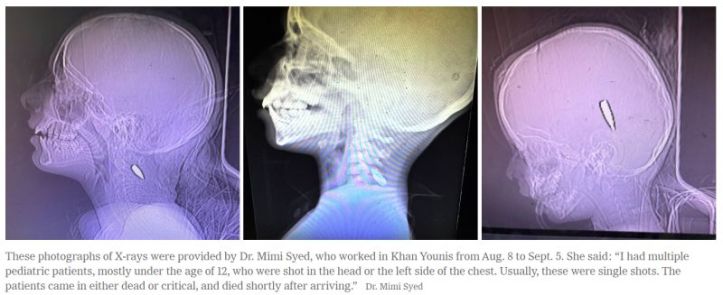

The New York Times reports that 44 out of 65 American doctors who have volunteered recently in Gaza’s almost destroyed hospitals, have seen children brought in with one bullet lodged in their brain or left side of their chest, right where doctors place their stethoscopes.

Sometimes a sniper pumped one bullet into a child’s chest and another into their brain. As US orthopedic and hand surgeon Dr Mark Permutter said, “No child has been shot twice by mistake by a sniper.”

Perlmutter spent nearly a month last spring in Gaza’s hospitals. He has definitive proof that Israeli sharpshooters targeted young children, and he knows. “On our medical teams we have vast experience with high velocity bullet wounds. The children were hit with such high velocity that their entire chest cavity is missing. We turn the child over and we see their spinal cord, their lungs and hearts were never brought into the operating room.”

Given that Gaza’s few remaining hospitals are hanging on by a thread, that there are few analgesics, and no operating theatres, dressings or supplies, these children with the single bullet die within hours or days because the bullets remain buried in their little bodies.